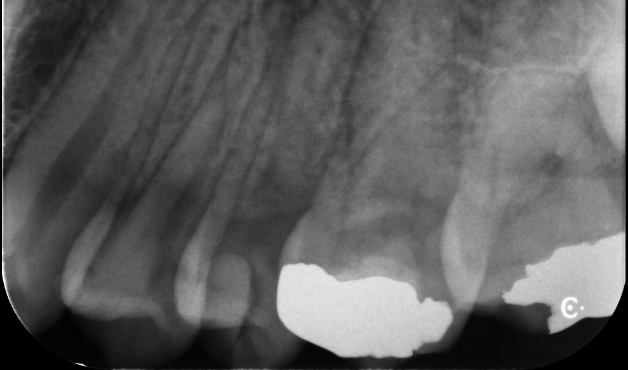

再根管治療と外科的歯内療法を組み合わせて

歯を残した症例

タップで写真の拡大ができます。

Before

After Retretment

After Endodontic Microsurgery

術前

術直後

術後1週間

主訴

歯ぐきの腫脹

診断

根尖性歯周炎(根尖吸収、パーフォレーションを伴う)

治療方針

歯の保存を希望されたため、まず再根管治療を行った。

治療中に近心根にパーフォレーションを認め、MTAセメントによる封鎖および根管充填を行ったが、経過観察において症状の改善は得られなかった。

根管内からのアプローチでは感染源の除去に限界があると判断し、外科的歯内療法へ移行した。

治療内容

再根管治療、MTAセメントによる封鎖、レジンコア、外科的歯内療法

治療期間

約6ヶ月(経過観察期間を含む)

治療費用

330,000

結果

再根管治療では症状の改善は認められなかったが、外科的歯内療法後には症状は消失し、現在まで再発なく機能している。

治療の

リスク

根尖病変が完全に消失しない可能性

考察

パーフォレーションを伴う症例では、根管内からの処置のみでは感染源の除去に限界がある場合がある。

本症例では再根管治療を先行した上で外科的歯内療法を行うことで、より確実な感染源の除去が可能となった。

適切なタイミングで外科的アプローチへ移行することが、 保存の可能性を高める上で重要である。